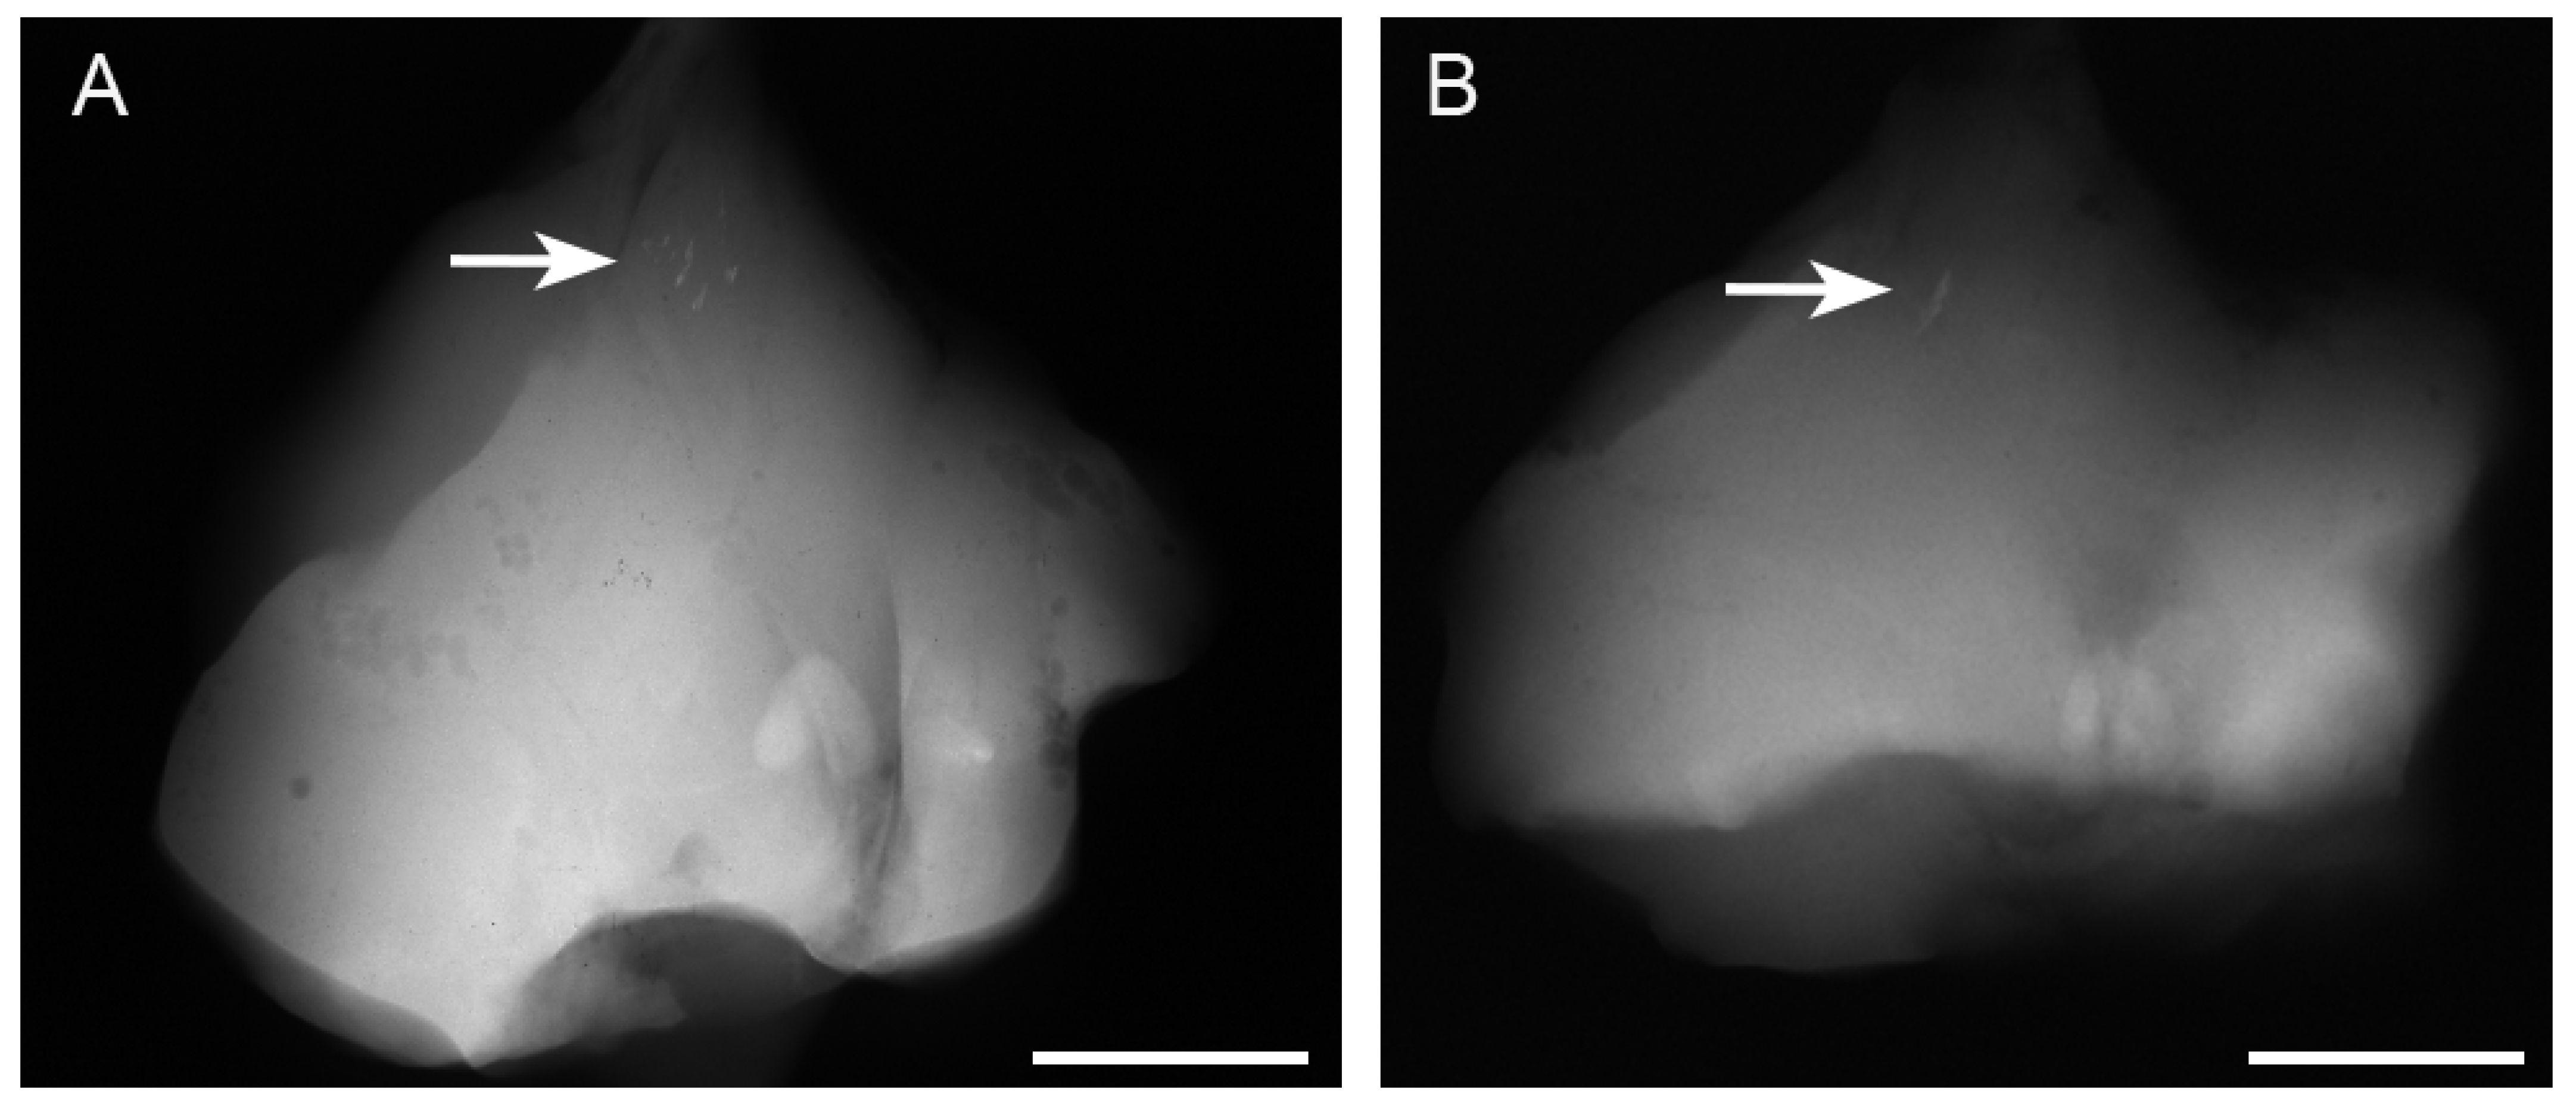

Radiographs revealed opacities comprising several small calcified particles with clear margins in the muscles targeted for bmp-2 transfection via in vivo electroporation using needle-type electrodes (Figure 2A). The opacities were detected in all six rats (100%). In vivo electroporation using plate-type electrodes resulted in large opacities with clear margins in the targeted muscles (Figure 2B) in two out of six rats (33%). The average areas of each particle-containing opacity were 0.071 ± 0.048 mm2 (needle-type electrode) and 0.494 ± 0.54 mm2 (plate-type electrode) (Figure 3A). The average areas of total particle-containing opacities were 0.31 ± 0.376 mm2 (needle-type electrode) and 1.135 ± 1.082 mm2 (plate-type electrode) (Figure 3B).

Figure 2.

Presence of opacities on soft X-ray films after bmp-2-expressing plasmid electroporation. The opacities (white arrow) in the targeted muscles after electroporation with (A) needle- and (B) plate-type electrodes. Several opacities (white arrow) in the skeletal muscle bmp-2 gene were transferred with needle-type electrodes (A). One opacity (white arrow) was found in the skeletal muscles with plate-type electrodes (B). Each scale bar is 15 mm.